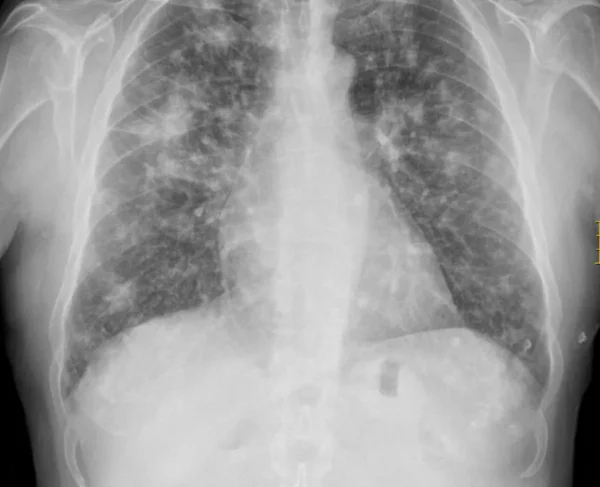

La esporotricosis es una infección micótica crónica que se desarrolla a partir de la inoculación en la piel de hongos pertenecientes al complejo Sporothrix schenckii. Este complejo agrupa varias especies…